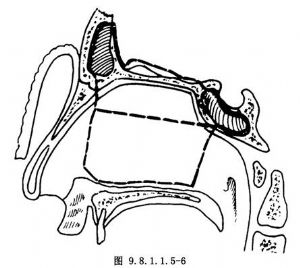

病變範圍較小,主要位於鼻腔上部和篩區,鼻底和上頜竇外下部未受侵犯者,爭取保留上齶,這對於減少口腔和咽部向顱底的污染,及保存病人術後口腔功能都有利。此術式基本採用Sisson's篩骨及鼻腔上頜側壁大塊切除術式。做鼻側切開術,切口起自眉弓內端,向下順鼻側過鼻翼而至鼻翼外腳,切開鼻前孔,分離鼻骨,連同鼻翼前上翻轉,充分顯露鼻腔(圖9.8.1.1.5-5)。切斷內眥韌帶,沿眶內壁分離紙樣板,探查紙樣板有無骨質破壞。電燒切斷篩前動脈,分離達眶尖,上方與顱內切開線相連。分離淚囊,切斷鼻淚管,向外上牽引眶內容,分離眶底至眶尖。切開上脣,分離並翻開頰側軟組織瓣。於尖牙窩區鑿骨窗,探查上頜竇,若證明其底部及外側壁可以保留,將竇骨黏膜分離連於竇內上角。於眶下孔處切開眶下壁骨板達眶尖。於鼻底處切開鼻腔側壁達翼突,完成外側及下方遊離。下一步是暴露鼻腔上部與顱內切開線。若鼻腔上方術野顯露尚不夠,可分離對側鼻骨,切開鼻中隔,全翻鼻錐而擴大術野。於中部橫形切開鼻中隔,並於前後向上切開與顱內切開線相接(圖9.8.1.1.5-6)。至此,除師竇及鼻腔側壁後部尚與蝶骨體及翼突連接外,腫瘤四周全部遊離。用彎剪經顱內後方切開線伸入,剪開後方上部連接,並用手指向下推壓已遊離之前顱底區,使標本向前下移位。再用彎剪,由面部術區伸入後方,剪開標本後部下方之連接,全部標本即可由面部取出(圖9.8.1.1.5-7)。後篩區與蝶體和眶尖連接部分常不能一次徹底切下,需要局部再次修切。